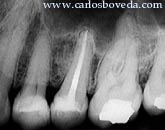

Incisivo

Lateral Superior Derecho

Central Superior Derecho